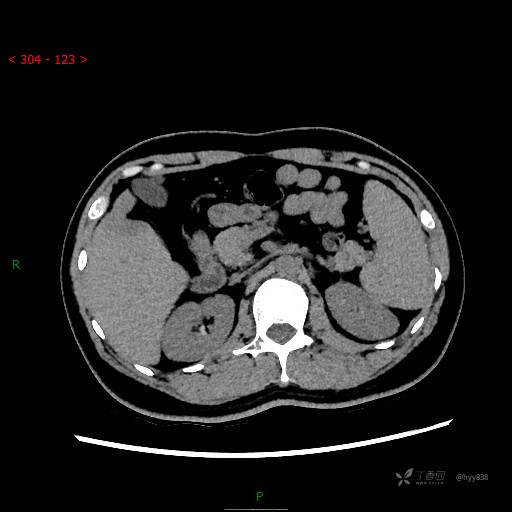

延迟期